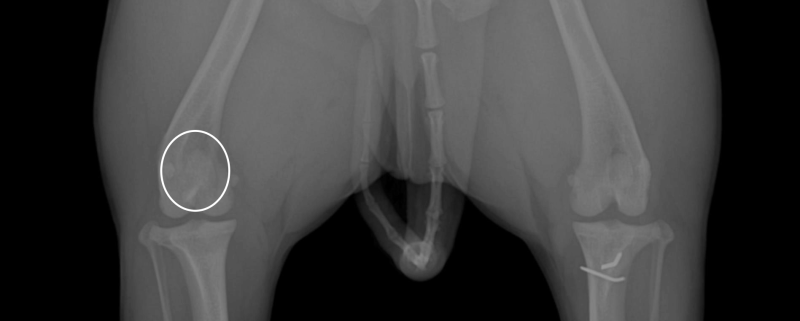

환자의 뒷다리 방사선 사진 / 환자의 왼쪽 다리 세부 사진

환자의 방사선 사진입니다. 오른쪽 다리는 1기, 왼쪽 다리는 슬개골 탈구 3기 진단을 받았습니다.

사진에 보시면 왼쪽 다리의 경우 정상 위치(무릎의 중앙)에 있어야 할 슬개골이 내측으로 빠져있는 것을 볼 수 있습니다.

아직 슬개골 탈구가 1기인 오른쪽 다리는 무릎의 중앙에 위치하고 있는 것을 비교하여 볼 수 있습니다.